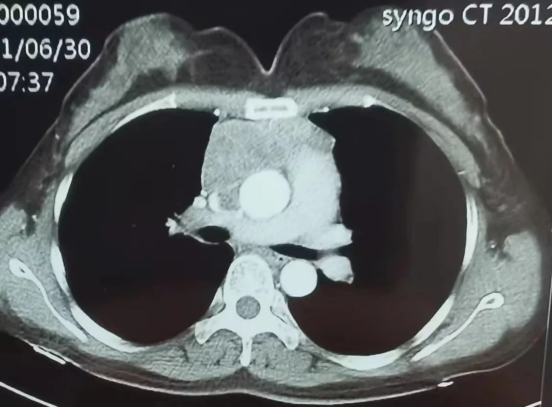

此前,心胸血管外科团队已于今年3月份开展我市首例胸腺肿瘤切除、上腔静脉人工血管置换术,填补该项技术空白。此例恶性纵隔肿瘤切除、上腔静脉及左无名静脉人工血管置换术的成功开展再次展示了医院心胸外科在高难度复杂手术上雄厚的技术实力和高超的技术水平。今年5月,35岁的张女士突然出现左上肢、左侧颈部肿胀。向来无病无痛、也没有外伤,怎么突然出现这个症状呢?对于身体突如其来的变化,不仅张女士的家人想不明白,她本人更是感到莫名其妙。然而,当她到医院经胸部CT检查后,医生的检查结果则令其瞠目结舌。

原来,引起张女士左上肢、左侧颈部肿胀的原因,是其体内上腔静脉有一约6.4cm左右的肿瘤严重压迫静脉血管所致。随后,医生对其肿瘤穿刺被诊断为恶性胸腺瘤。

11月,患者慕名前往广元市第一人民医院心胸血管外科再次就诊。胸部增强CT检查发现,发现患者上腔静脉肿瘤缩小至4.3cmx1.2cmx3.9cm,左头臂静脉九成以上成闭塞状态,上腔静脉中度狭窄、上腔静脉癌栓……放射科进行上腔静脉血管三维重建,对患者病情反复对比研究,认为手术时机已到!